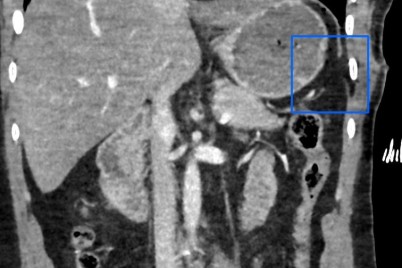

تمكّن باحثون في كلية الطب بجامعة كاليفورنيا، من الكشف عن دواء واعد جديد يعمل على الحد من التليف الكبدى...